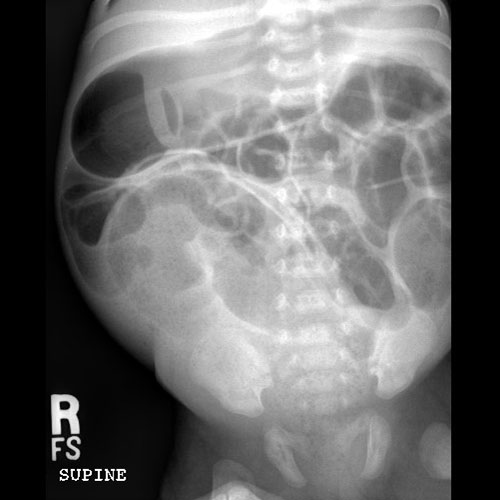

KUB/Supine Abdomen.

Scout Image of the abdomen

There is dilatation with gas or fluid of multiple or diffuse loops of bowel.

​Both the small and large bowel are filled with air and/or fluid and may or may not be distended.

There are centralized loops of small bowel with distention of the abdomen and pelvis.